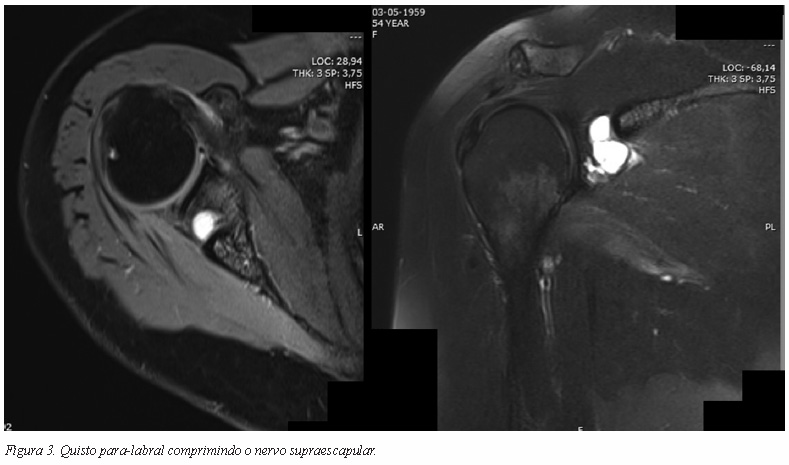

A compressão pode também acontecer na goteira supraescapular ou na chanfradura espinoglenoideia por um mecanismo direto, como seja a presença de um tumor dos tecidos moles, um tumor ósseo, uma malformação vascular, ou mesmo um quisto secundário a lesão capsular ou do labrum (Figuras 2 e 3).

A neuropatia do nervo supraescapular na chanfradura espinoglenoideia é tipicamente secundária a compressão do nervo por lesão ocupando espaço. A maioria destas lesões são quistos, normalmente secundários a lesões do labrum, lipomas ou outros tumores benignos da região27, 53.

Quando o motivo da compressão é um quisto, a questão é bem mais controversa. Alguns autores propuseram a aspiração do quisto guiada por ecografia mas os resultados foram inconsistentes. Vários estudos apontam para um bom alívio da dor32, 54-56 mas com taxas de recorrência elevadas (até 75%)57, 58. Pare ser uma técnica segura mas com alta taxa de recorrência provavelmente devido ao facto de não abordar a patologia de base.

O tratamento cirúrgico pode consistir numa descompressão cirúrgica do quisto por via aberta ou artroscópica, associada ou não à reparação do labrum, ou pode consistir apenas numa reparação isolada do labrum. A descompressão aberta pode ser efectuada por via de abordagem posterior do ombro. Contudo, esta via oferece uma visualização limitada do labrum e de outras possíveis lesões intra-articulares associadas46. A via artroscópica é mais versátil permitindo a descompressão do quisto bem com a visualização e tratamento das lesões intra-articulares. Diversos autores como Westerheide, Chen e Lichtenberg defendem um risco de recorrência menor na via artroscópica46, 57 bem como uma melhoria funcional mais consistente após a descompressão do quisto e reparação do labrum59, 60.